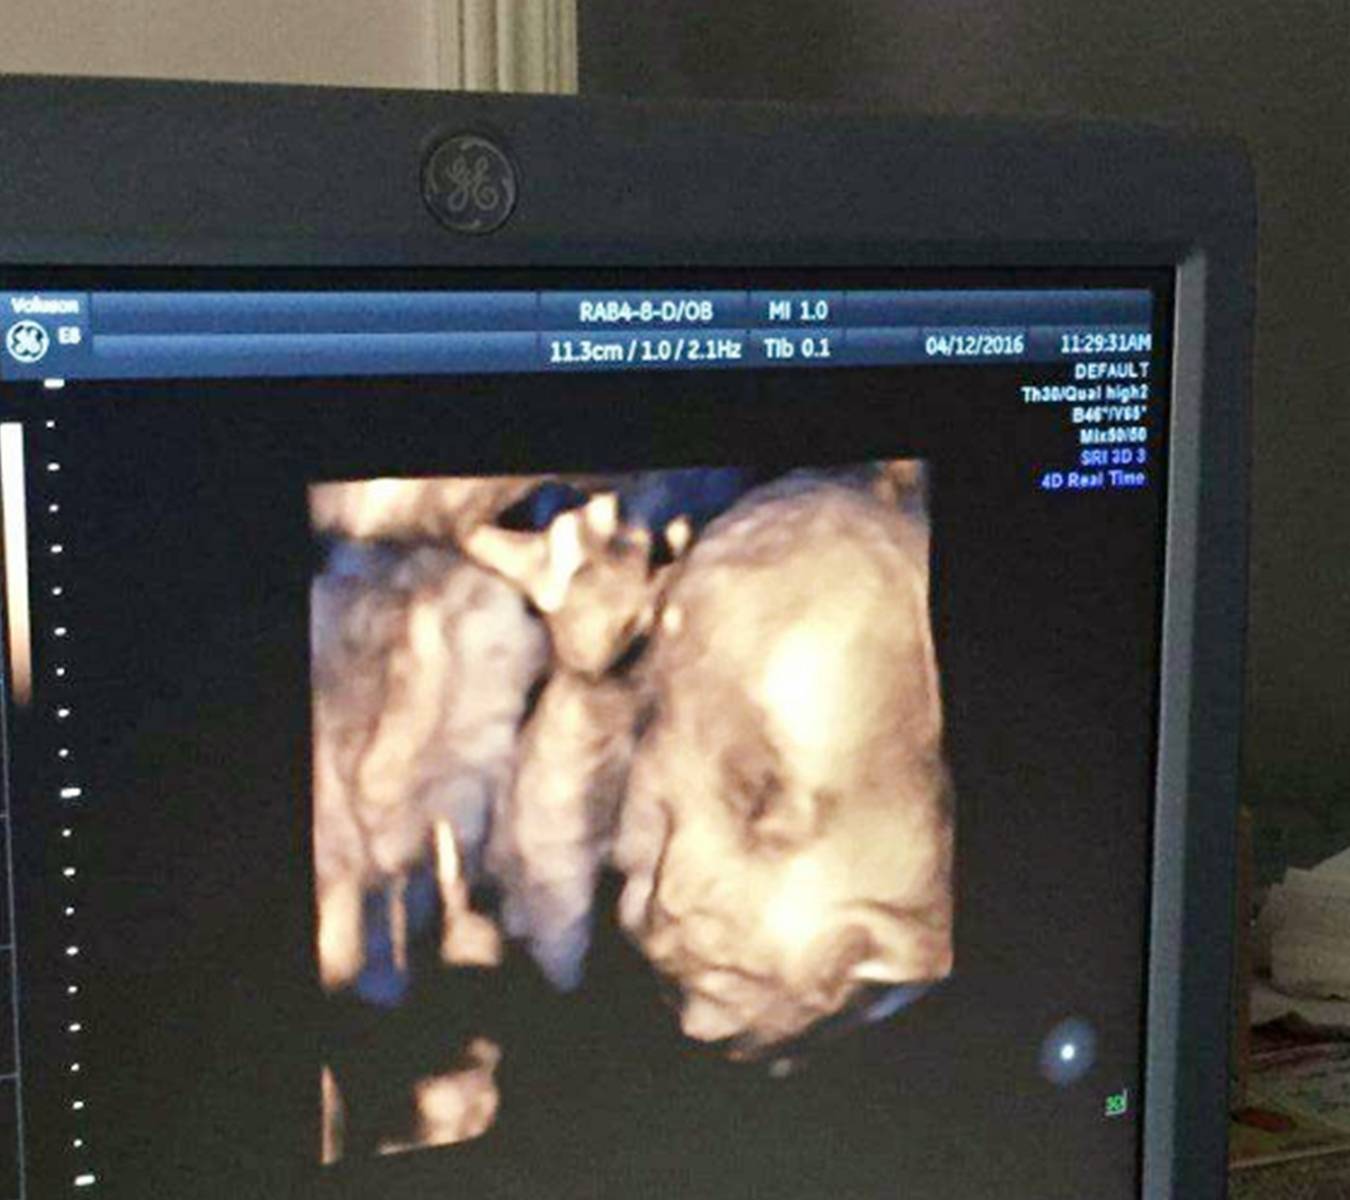

3) 大排畸

大排畸的检查是必须要做的 , 也是孕期判断胎儿是否发育畸形的最直接的检查方式 。

大排畸能看到胎儿的大致模样 , 宝宝的身体各项发育情况都能看到 , 最大的用处就是判断胎儿发育有无畸形 , 以便医生对胎儿是否能继续发育做出判断 。